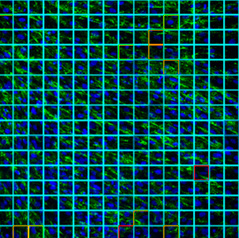

Visualització del diagnòstic d'una imatge de cultiu de fibroblasts. Les diferents zones de la imatge s'avaluen de forma independent cosa que permet identificar ràpidament àrees amb defectes en el col·lagen VI. El sistema també proporciona un diagnòstic general per poder fer un seguiment dels pacients.